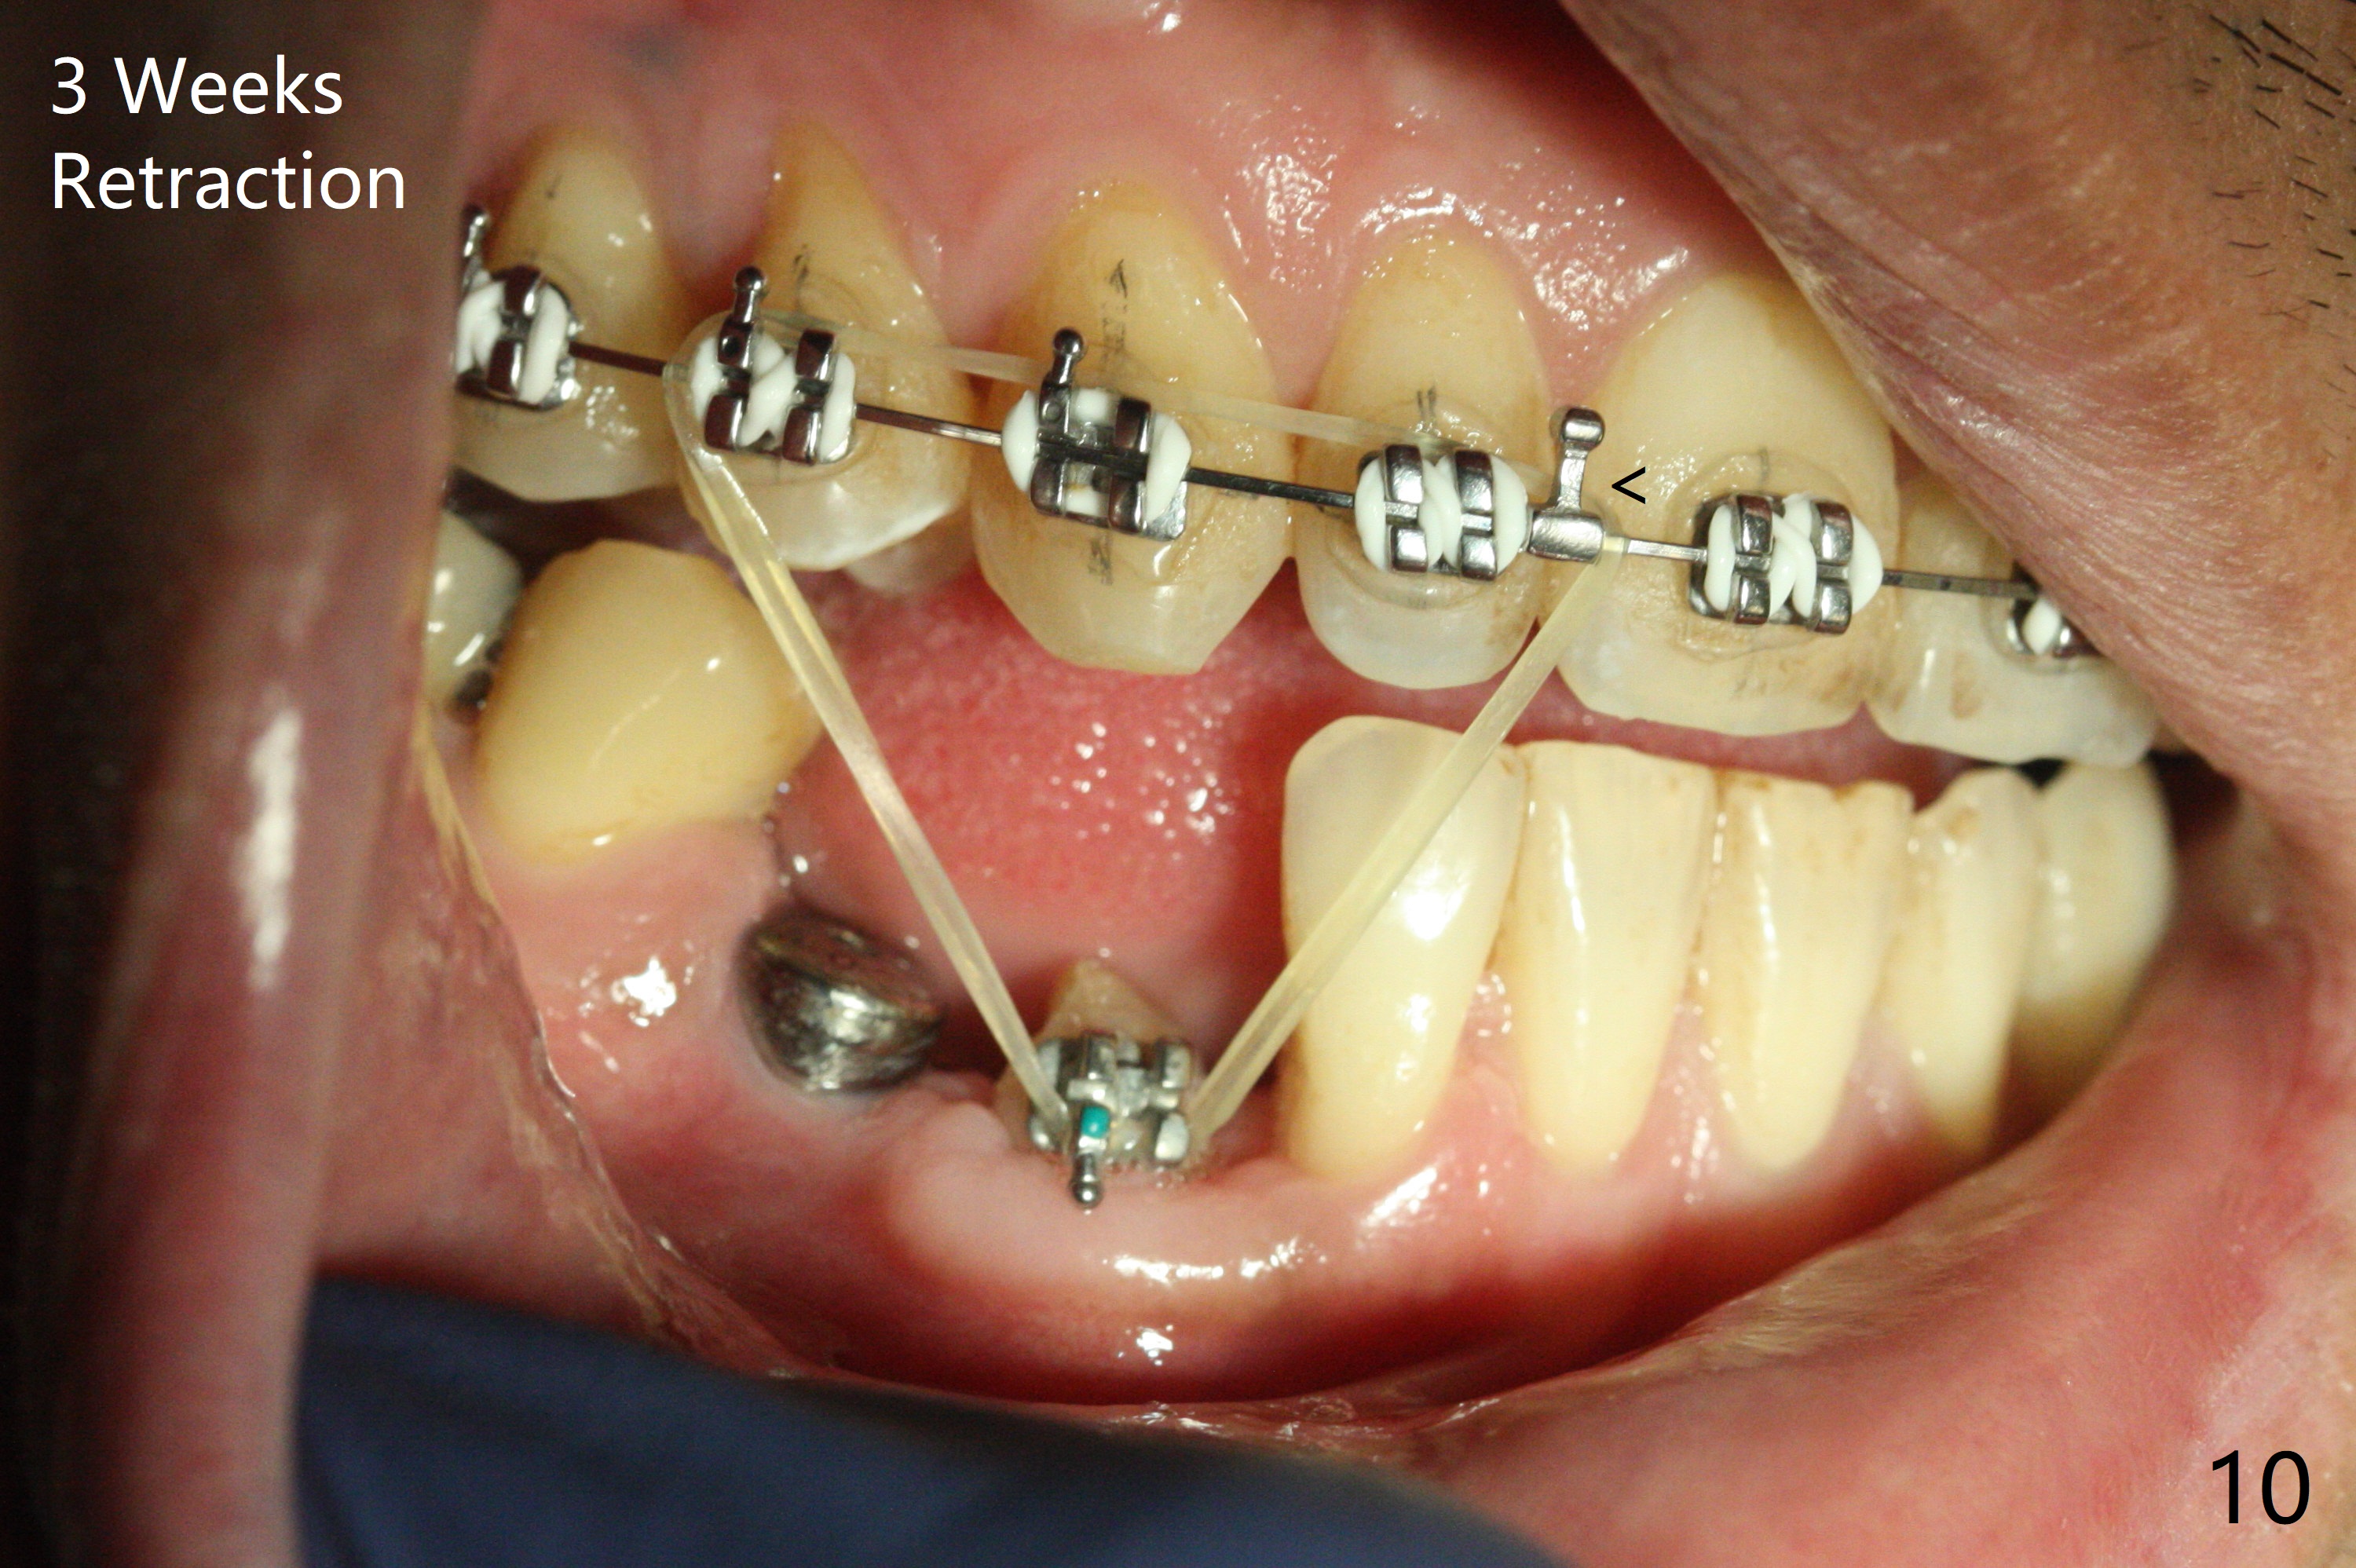

When the surgical guide for #28 is removed, the 4x13 mm implant is found to be superficial and buccal. Part of the buccal mucosa is nonkeratinized. After 1 mm deeper placement of the implant, CT confirms the buccal placement (Fig.1, as compared to design). In fact the guide was doubly checked for fitness prior to osteotomy, but grossly it seemed to be seated properly. The suspicion is related to the trimming at the site of #27 (Fig.2,3 (*), as compared to a mounted model in Fig.4,5 (arrowhead) and the model sent to lab for guide fabrication). The lab agrees to redesign the case. There is a narrow buccal band 1 week postop (Fig.6). The patient is a smoker. The implant was placed buccal (Fig.7, 1 month postop). A new 4x13 mm implant is placed on the top of the 1st line following 3x14.5 mm drill (Fig.8 (35 Ncm)). In fact the implant position is not changed much. Four months post banding (20 ss) and 2 months post 2nd implant placement, the tooth #27 is exposed for bracket; extrusion is initiated (Fig.9). In 3 weeks of retraction, the bracket is supragingival (Fig.10). The canine contacts the distal healing abutment with 2 months of retraction (Fig.11). It seems necessary to initiate lower bracket placement. There is no bone loss 4 months postop (Fig.12). A 4.5x7(4) mm abutment is placed (Fig.13) for a temporary crown as an anchor (Fig.14) to further extrude #27 with continuous inter-arch retraction (to reduce tension upon #26 with severe bone loss (Fig.12)). LR3 extrusion is incomplete, although there is an increase in bone distal to LR2 ~ 10 months of extrusion (Fig.15).